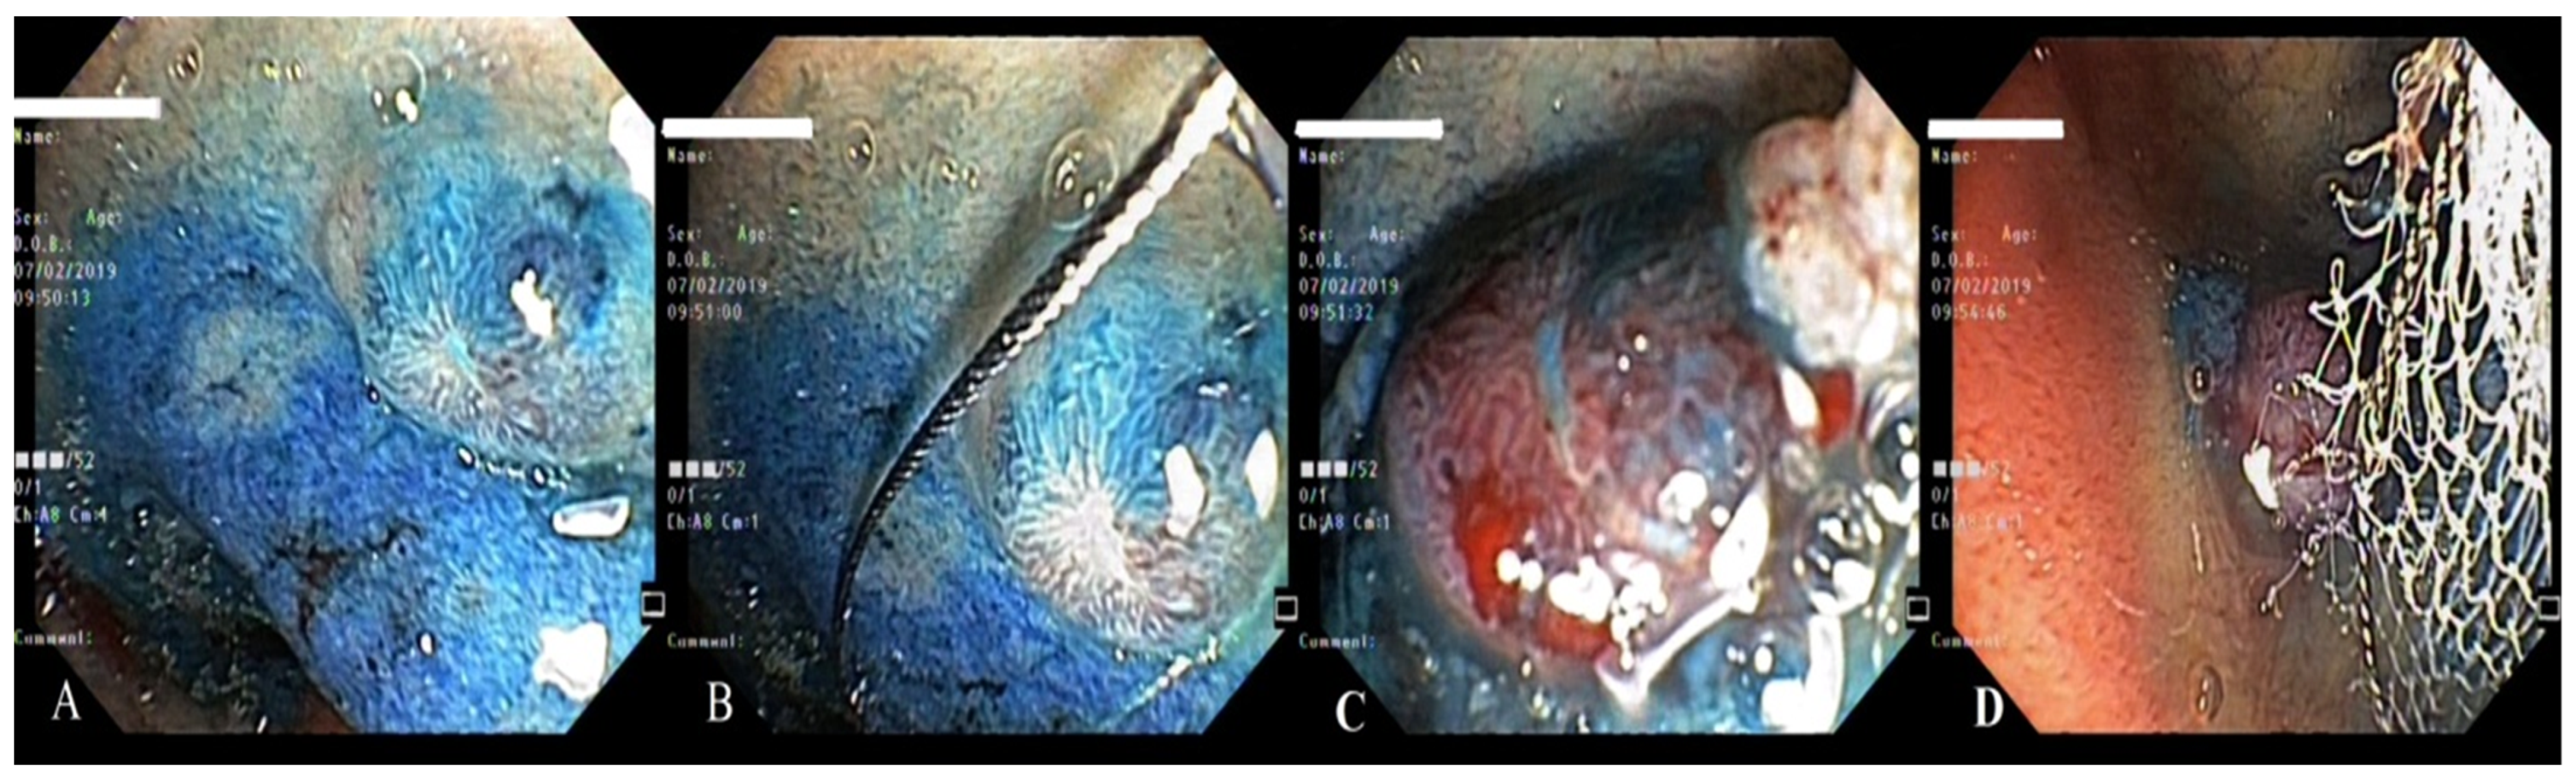

4. Case Report 3